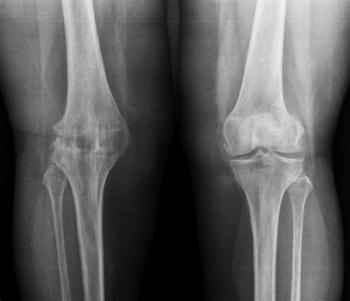

Рентген коленного сустава

При травмах ног различной тяжести, заболеваниях или возрастных изменениях, развивающихся в костно-хрящевых структурах, нередко возникает необходимость в рентгене коленного сустава.

Проникающая способность рентгеновского излучения позволяет получать детальные и четкие снимки костной и хрящевой ткани колена, а также получать представление о состоянии прилегающих мягких тканей.

Полученные изображения помогут травматологу или ортопеду выбрать наиболее правильную схему лечения либо проконтролировать его результат.

Классикой исследований является рентген коленного сустава в двух проекциях: прямой и боковой. Однако на самом деле их может быть больше, к тому же снимки нередко делают в двух позициях: лежа и с нагрузкой, т. е. стоя.

На рентгеновских снимках специалисты отчетливо различают переломы и трещины в костной ткани, вывихи, разрывы и растяжения связок, повреждения надколенника, признаки артроза или артрита, различные новообразования, признаки остеопороза и остеомиелита, врожденные аномалии строения костей и другие патологии.